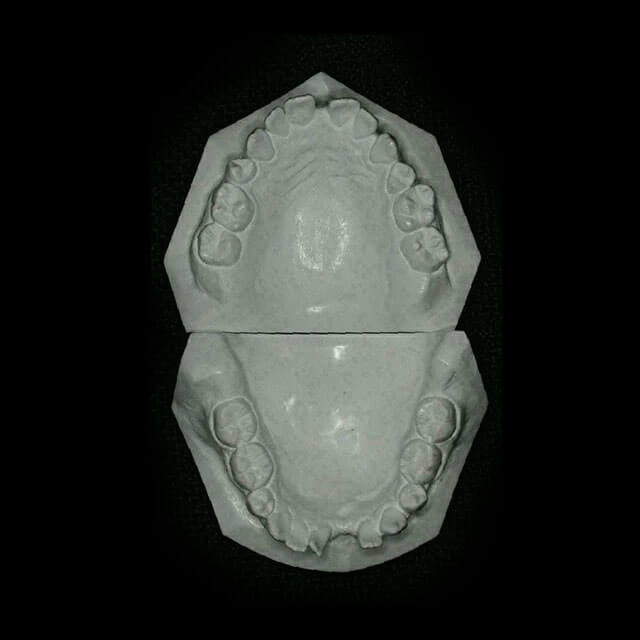

A documentação ortodôntica é um conjunto de exames composto por radiografias, fotografias intra e extra-bucais, modelos em gesso das arcadas dentárias, análises cefalométricas e de modelos computadorizados que o dentista solicita para ter uma visão abrangente e detalhada do caso de seu paciente.